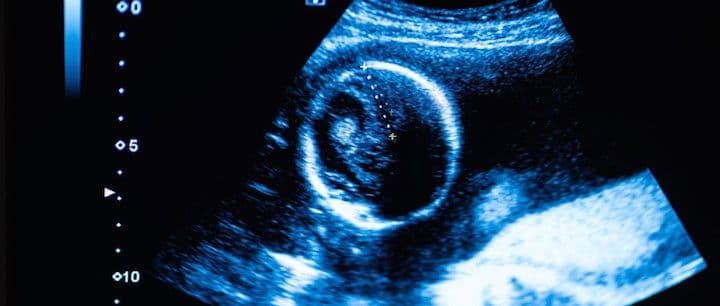

You may have had a positive pregnancy test but when will you be able to have an ultrasound to confirm the pregnancy?

The first part of the pregnancy that can be seen is the gestational sac. The gestational sac can be seen around cycle days 32-35, which is about 18-21 days after ovulation/fertilization. However, sometimes it can take a couple of days longer to see the gestational sac on transvaginal ultrasound. On abdominal ultrasound, the sac can be seen several days later.

The gestational sac is a structure that surrounds the embryo and can be seen even before the embryo is visible. About 7-10 days later, the embryo can be seen on transvaginal ultrasound (at approximately 6 weeks, 3 days). You can likely now also see the fetal heartbeat.